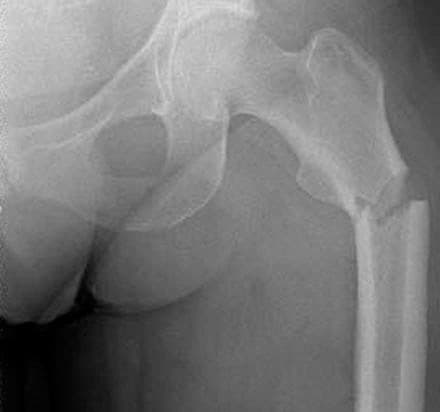

En 51-årig kvindelig epileptiker uden komorbiditet blev indlagt med AFF efter et fald fra egen højde. Hun havde ti år før hændelsen fået konstateret epilepsi, men gennem flere år været anfaldsfri på lavdosislamotriginbehandling og fik ikke anden medicin. På røntgenbilledet konstateredes nonkomminut subtrokantær tværfraktur med tydelig fortykkelse af den laterale vs. den mediale cortex. Resultaterne af de præoperative blodprøveanalyser var upåfaldende, der blev dog ikke målt calcium- og D-vitaminniveau. Patienten fik indopereret et langt gammasøm og havde et kirurgisk ukompliceret efterforløb. En opfølgende knoglescintigrafi var uden patologiske fund, og der var god heling af frakturen.